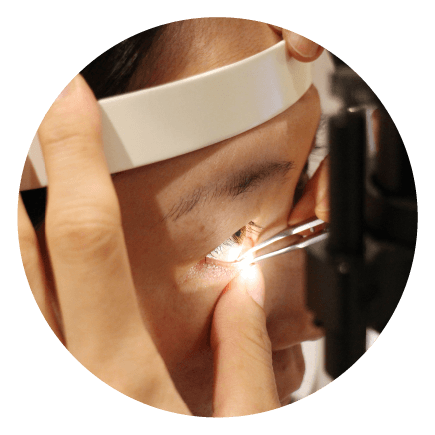

アイプロテクトで眼球を保護しIPLを照射する

マイボーム腺圧迫セッシでマイボーム腺のつまりを解消します